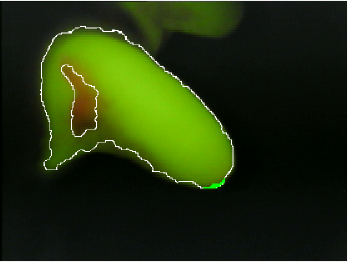

The biofilm quantification index computed during the first phase of computer-aided biofilm quantification closely follows manual scoring results. The algorithm has been evaluated on 470 images. The results are highly consistent with the manual gradings. Fig. 5 shows an initial-guess quantification on a set of dental images for two teeth taken over a period of 6 months.

Refer to caption

(a)

(b)

(c)

(d)

Figure 5: The quantification maps produced by the proposed automatic quantification algorithm for QLF images (pre-expert tweaking). Two teeth from the same subject are scanned over a period of 6-months to quantify plaque over time. (a) shows a premolar canine tooth at month 0, (c) shows the same tooth after 6 months. (b), and (d) show a molar teeth of a canine imaged at the start of the study (month 0) and month 6 respectively.